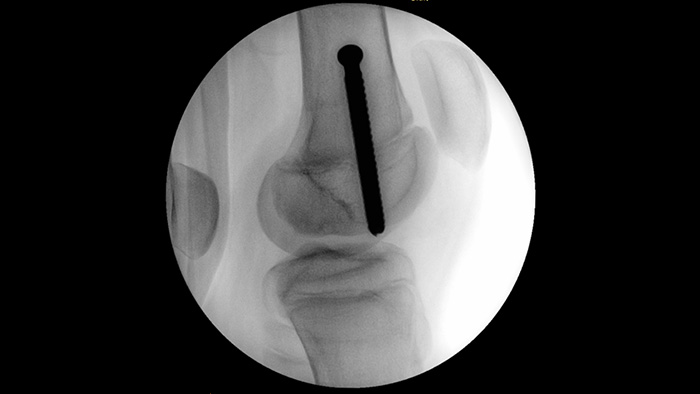

MetalSmart automatically excludes metal artifacts caused by metal implants to provide higher image quality and efficient dose control during orthopedic procedures and patients with metal implants, compared to systems without metal exclusion. BodySmart promotes first-time-right imaging and dose efficiency by automatically adapting the measuring field to the area of interest.

When setting pedicle screws for a spinal fusion or fracture repair, reducing technical distractions and discussions can help surgical teams remain focused on the patient. With Unify workflow’s navigation aids, surgical teams experienced smoother interactions and less miscommunication in a usability study.1